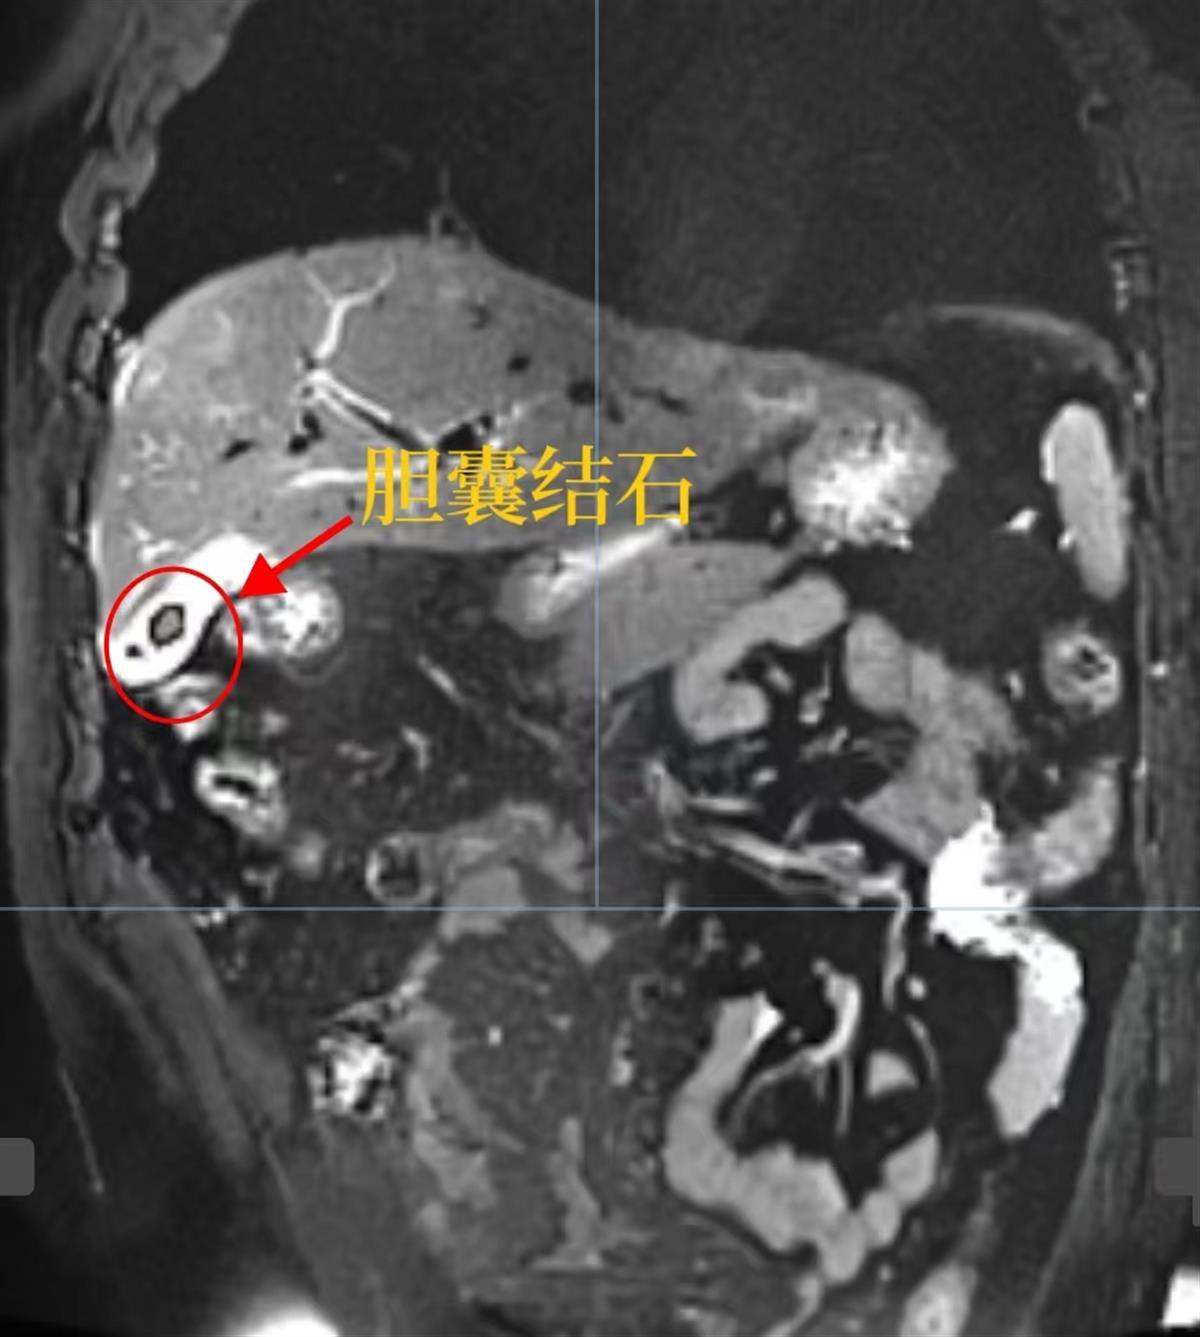

由于腹部伴有明显的剧烈绞痛,林先生到达武汉市普仁医院时,因疼痛难忍加上一直叫喊,导致声音都已经嘶哑,医生们立即为其急查腹部,CT检查提示“胆囊结石伴慢性胆囊炎急性发作”,其胆囊里有2颗大小约6毫米的结石,遂马上将其转至武汉普仁胡海胆石病医院,并立即给予解痉止痛、护胃、护肝、补液等对症处理,同时完善各项检查。

林先生胆囊里的2颗结石

检查结果显示,林先生肝功能严重受损,且在护肝等对症处理后第二天复查时发现其相关指标不降反升。此时,林先生的巩膜和皮肤已经开始发黄,磁共振结果显示,其胆结石已经“掉”到了胆总管。